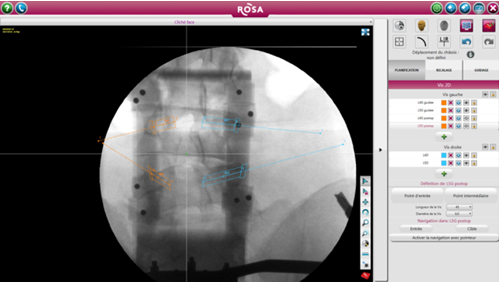

ROSA 是一種影像導航設備,直接根據術中放射線圖像上確定的標志或使用導航指針定位工具。引導是基于術中2D圖像處理軟件完成的軌跡規劃,隨后患者俯臥位完成注冊(圖1)。在手術開始時,沿著患者的右手邊放置機器人,確保機器人的手臂能充分地覆蓋兩個節段(圖2)。然后外科醫生站在患者的另一邊。手術室的組織結構圖如圖3所示。

圖1術前X線透視下椎弓根螺釘的規劃